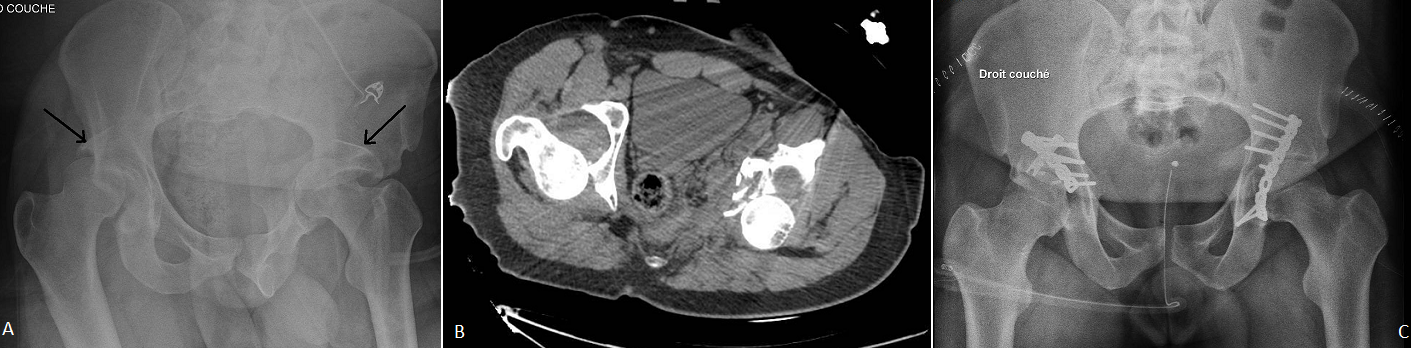

La fracture luxation centrale du cotyle est une lésion rare et nécessite un traumatisme violent, l'association de deux lésions similaires est encore plus rare, au mécanisme souvent imprécis et le choc doit être très violent, et donc elles se présentent dans le cadre de polytraumatisme, d'où l'intérêt de les rechercher systématiquement. Nous rapportons l'image d'un patient de 26 ans victime d'une chute d'échafaudage, présentant sur le plan locomoteur un traumatisme fermé des deux hanches .Le bilan radiographique a montré une fracture de la paroi postérieure des deux cotyles associée à une luxation postérieure des 2 têtes fémorales (A, B). Le patient a bénéficié en urgence d'une réduction orthopédique par traction des deux membres puis à j+3 d'une ostéosynthèse des deux cotyles en un seul temps par 2 voies de kocher langenbeck (C). À cinq mois, la récupération fonctionnelle des hanches est presque totale surtout à gauche. Le pronostic fonctionnel de ce type de lésion dépend de la précocité de la prise en charge.